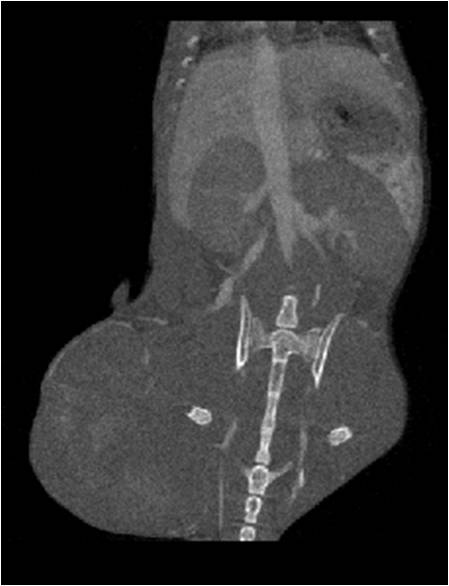

• 能進(jìn)行肝、脾、腎等內(nèi)臟的成像研究,獲得體積、表面積等定量參數(shù)。

腫瘤血管生成

肺纖維3.jpg